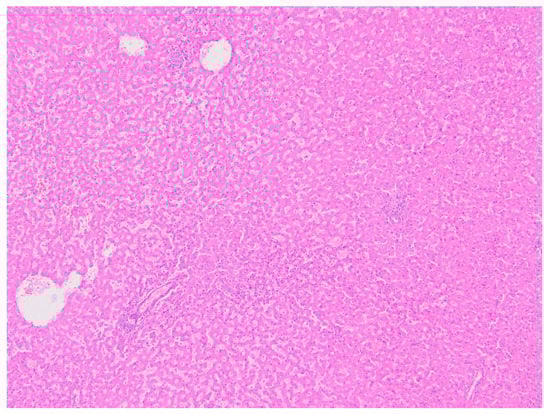

5.1.5. Histopathology and Immunohistochemistry